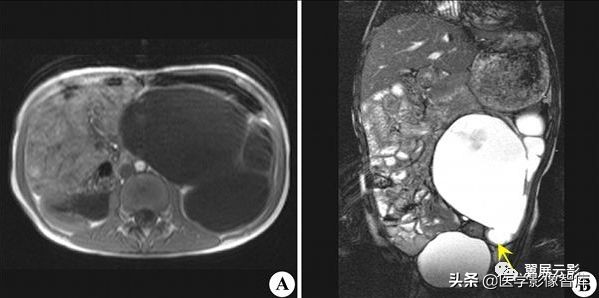

多囊肾

本病常合并多囊肝,此为先天性常染色体显性遗传性疾病,多数学者认为多囊肝是在多囊肾的基础上基因突变的结果,并定位于16号染色体上,也有学者认为该病是由于胚胎发育不良所导致,于胚胎早期管道形成时排列失常,造成无数迷管,于胚胎晚期未退化,且逐渐扩张成囊,成多发性囊肿病,根据发病年龄的不同,将其分为儿童型和成人型,本病多发生于双侧肾脏,可继发感染,结石以及囊内出血和囊壁钙化,也可以恶变,并有阻塞性黄疸及合并皮下囊肿的报道,临床上早期无症状,就诊时肾脏功能已经不同程度受损,肝功能受损程度较轻。

MRI表现为双肾增大和分叶状轮廓,多发囊肿多数为长T1长T2信号,出血性囊肿可为短T1长T2信号或长T1短T2信号,增强扫描所有病灶均不强化,应同时视察合并的多囊肝及胰脾多发囊肿。